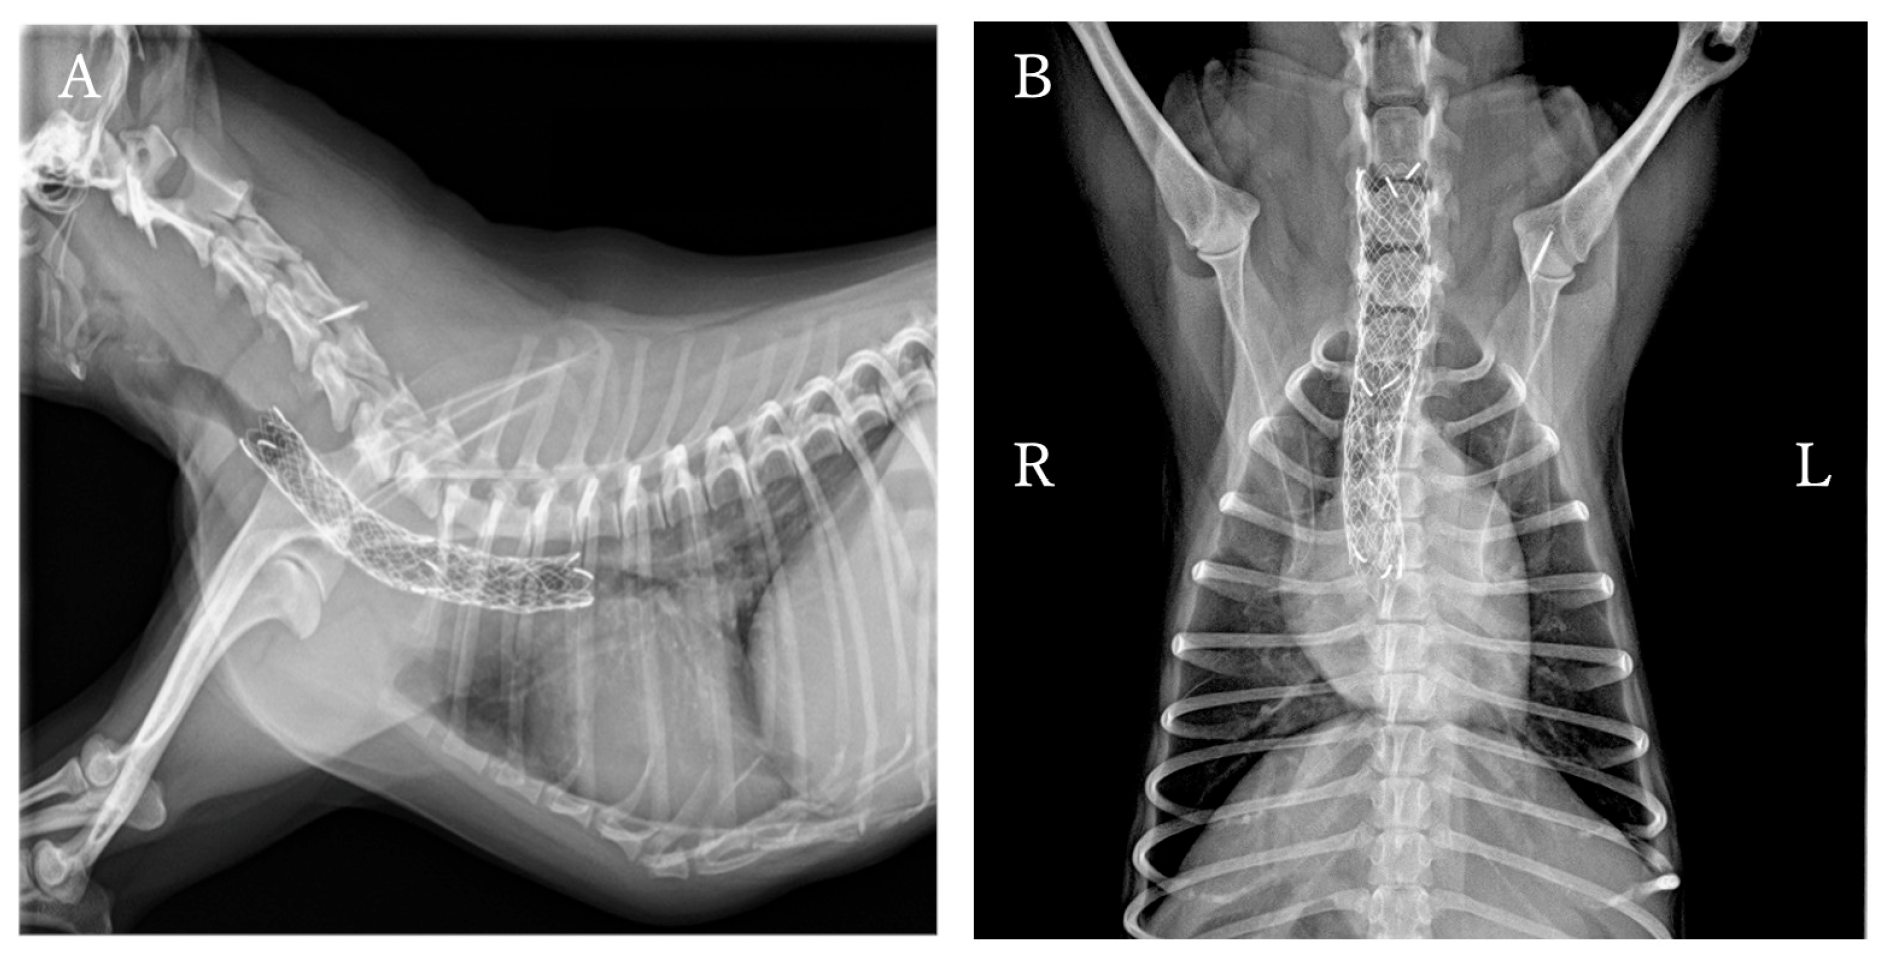

Thoracic and cervical radiography revealed severe narrowing of the trachea from the caudal aspect of the fifth cervical to the cranial aspect of the seventh cervical vertebra (Figure 1). The heart, pulmonary vessels, and pulmonary parenchyma appeared within normal limits. Fluoroscopy revealed persistent narrowing during both inspiration and expiration, leading to a diagnosis of static tracheal collapse. The patient exhibited cyanosis during the fluoroscopy, but this improved with oxygen administration (FiO2 0.4).

Figure 1. Cervicothoracic radiographs of the dog. (A) Right lateral view during inspiration. (B) Right lateral view during expiration. (C) Ventrodorsal view. The trachea was severely collapsed from the level of the caudal aspect of the fifth cervical to the cranial aspect of the seventh cervical. Arrows: the region of tracheal collapse.

Figure 3. Cervicothoracic radiographs of the dog in Figure 1 after placement of an endoluminal tracheal stent. (A) Right lateral view. (B) Ventrodorsal view. The stent spans and expands the area of tracheal collapse.